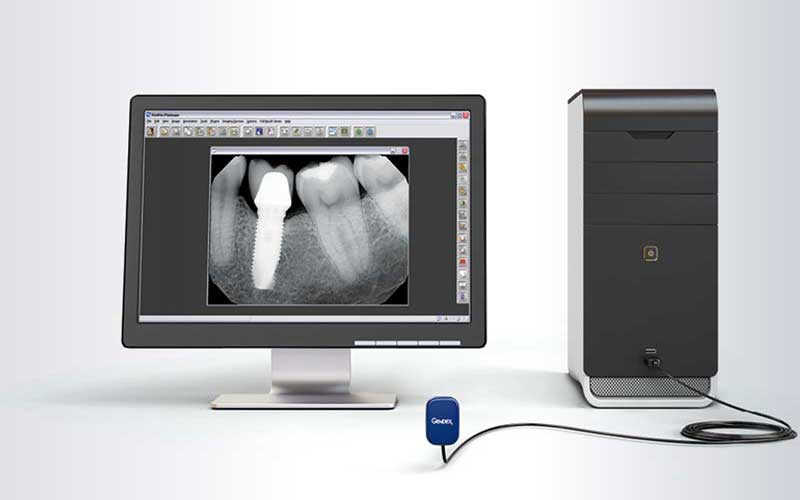

RVG(دستگاه رادیوگرافی دیجیتالی مدرن) : این نوع رادیوگرافی بسیار پیشرفته قابلیت عکسبرداری را به صورت دیجیتالی و با یک دهم میزان اشعه دارا می باشد.

تصاویری شفاف و دقیق در کمتر از 3 ثانیه بر روی کامپیوتر آماده و قابل چاپ می باشد و نیازی به کلیشه های قدیمی نیست. سیستم نرم افزاری بسیار پیشرفته و قوی با دسترسی آسان به تمام ابزارهای موردنیاز جهت هر گونه تغییر و تصحیح، امکان آنالیز تصاویر را در بزرگنمایی مناسب و دلخواه در اختیار دندانپزشک قرار می دهد. سیستم مونیتورینگ تمامی رادیوگرافی ها به صورت شبکه بر روی یونیت های کلینیک نصب شده و دسترسی به آن از تمامی مونیتورها امکان پذیر است. علاوه بر آن امکان داشتن کپی در آرشیو از تمامی فایل های ایجاد شده به صورت دیجیتالی بر روی کامپیوتر و همین طور نسخه چاپ شده آن وجود دارد. طراحی ویژه این دستگاه باعث جلوگیری از بروز آسیب به دهان بیمار در هنگام قرار گیری داخل دهان شده و سهولت در پوزیشنینگ را به همراه خواهد داشت.

رادیوویزیوگرافی دیجیتال (RVG) جدیدترین فناوری پرتوی ایکس در دندانپزشکی است. رادیوویزیوگرافی دیجیتال مجهز به نرم افزار آنالیز تصویری ویژه ای است که در آن این امکان فراهم شده است که تصاویر بزرگ شده و آنالیز شود و در پرونده بیمار ذخیره گردد. برخی از مزایای رادیوویزیوگرافی دیجیتال عبارتند از:

- حسگر دیجیتالی داخل دهانی که به جای فیلم پرتوی ایکس استفاده میشود

- ایجاد تصویر فوری در نمایشگر کامپیوتر